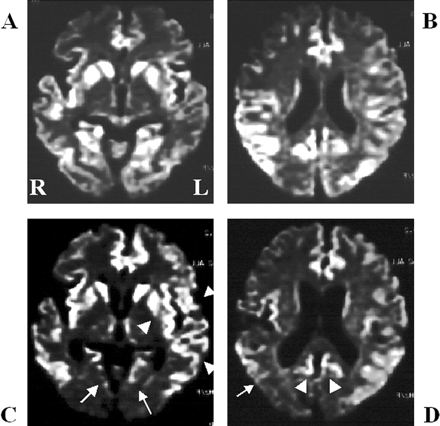

酒后驾驶是在26日检查库贾氏症患者发病后3到25周平均持续时间为10.7周。24库贾氏症患者表现出高强度脑损伤的驾车考试。两个观察者,醉酒驾车的库贾氏症诊断的敏感性为92.3%。interobserver协议率为100%。3例(12.5%)显示只在尾状头和硬膜损伤,10例(41.7%)患者显示线性损伤只有在大脑皮层,和11例(45.8%)患者显示病变基底神经节和大脑皮层(图1)。其中,只有三个病人(12.5%)显示,丘脑病变。没有病人显示高强度在小脑病变。高强度损伤在驾车之前出现脑萎缩。病变包括纹状体初并不总是对称的但是后来对称(图2),尽管对称的纹状体病变是众所周知的在库贾氏症。11在某些情况下,高强度损伤与连续驾车并不总是进展的疾病,而有时信号强度降低了疾病进展的一些病变。在某些情况下,皮质高信号强度不同,解剖分布(图3)。在终端阶段与深刻的脑萎缩,高强度损伤变得不清楚。T2I DWI-examined 26日在23日检查病人,但T2I扫描被排除在外,因为低质量由于运动构件。一位观察家认为11 22患者阳性(50.0%),而另一个观察者认为8阳性(36.4%)。interobserver协议率为68.2%,低于酒后驾车(p< 0.005)。在这两个观察者,醉酒驾车是比T2I更敏感(p一个观察者,< 0.005p另一个观察者p < 0.0005)。天赋是17 26患者的检查。一位观察家认为10 17例阳性(58.8%),和另一个观察者认为7是积极的(41.2%)。interobserver协议率为82.4%,也低于酒后驾车(p< 0.05)。醉酒驾车是比天赋更敏感(p一个观察者,< 0.01p另一个观察者p < 0.0005)。我们在图4一个例子中,只有醉酒驾车可以检测高强度异常病变。

图3。按时间顺序的改变皮质病变的零星克雅二氏症(sCJD)。皮质高强度在sCJD随着时间的推移而改变的情况下,增加和减少信号强度在不同的地区。高强度的双边枕叶皮层(A)减少(C,箭头),而信号强度在左岛和颞皮层(A)明显增加(C,箭头)。(一)和(C)之间的间隔是1个月。右颞叶皮层的高强度和双边枕叶皮层(B)减少(D,箭头为左颞叶皮层和箭头双边内侧枕叶皮层)。(B)和(D)之间的间隔是1个月。注意,高强度损伤中描述diffusion-weighted成像并不是简单地扩大疾病的进展。